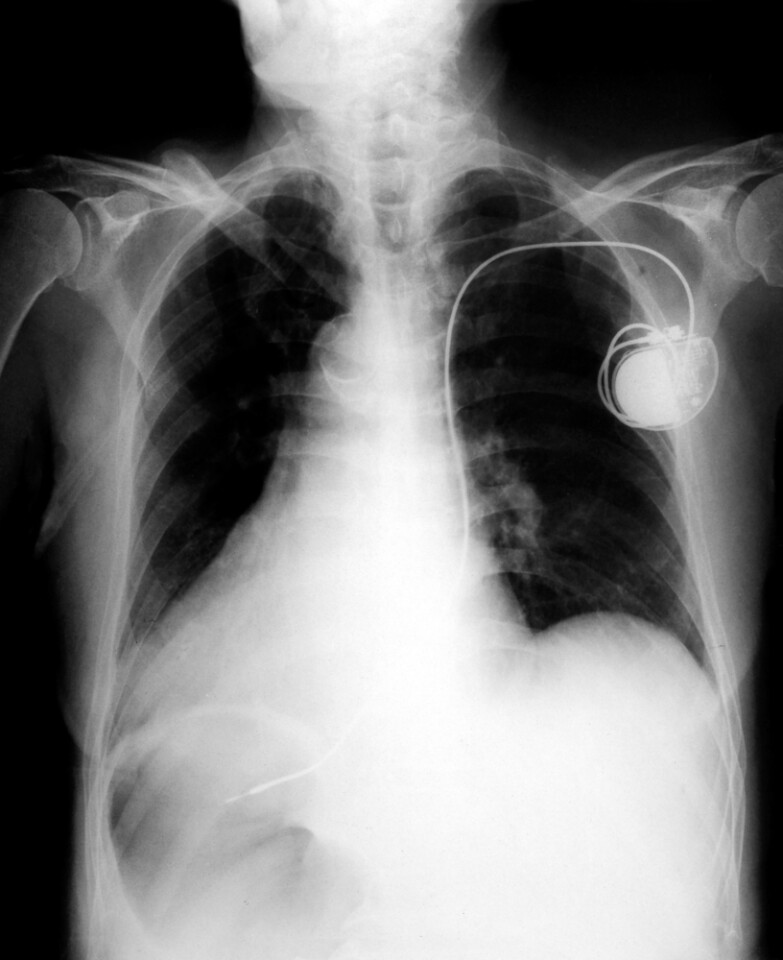

From tampacardio.com

Living With a Pacemaker Tampa Cardiovascular Associates Tampa, FL Piezo With Pacemaker Piezoelectric scalers do not produce. The piezo can also be used on all patients with pacemakers, whereas magnetostrictive scalers may not. The concern about using power driven scalers on patients who have cardiac pacemakers is limited only to magnetostrictive. For example, because ferromagnetic/magnetostrictive instruments may affect unipolar pacemakers, the dental. Modern cardiac devices are generally. Various studies have shown some. Piezo With Pacemaker.